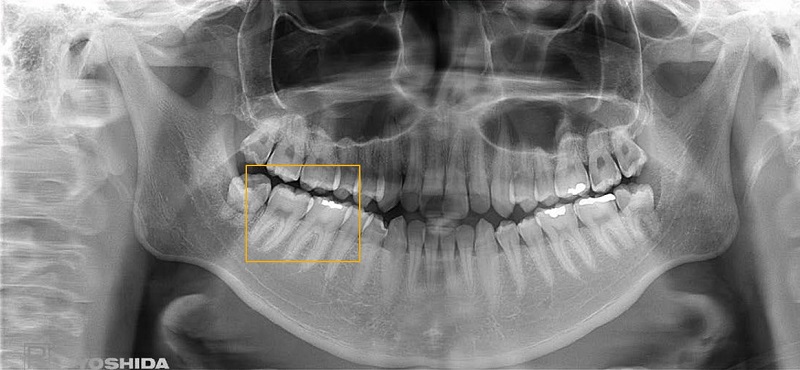

Thiết bị X-Quang toàn cảnh được các chuyên gia đánh giá là giải pháp chẩn đoán hình ảnh một cách toàn diện và có độ chính xác cao. Thiết bị này giúp hiển thị đầy đủ các góc chụp trong khoang miệng bệnh nhân, giúp các Bác Sĩ dễ dàng phân tích đánh giá và đưa ra kế hoạch điều trị hiệu quả nhất.

Chụp X-Quang toàn cảnh hàm răng

• Cung cấp hình ảnh 2D hoặc 3D (tùy thiết bị) mang đến cho Bác Sĩ cái nhìn trực quan, rõ ràng.

Thiết bị X Quang toàn cảnh Yoshida

Yoshida được nhiều chuyên gia đánh giá là thương hiệu thiết bị nha hoa chất lượng hàng đầu trên thế giới

Hình ảnh chụp toàn hàm từ X-ERA Smart